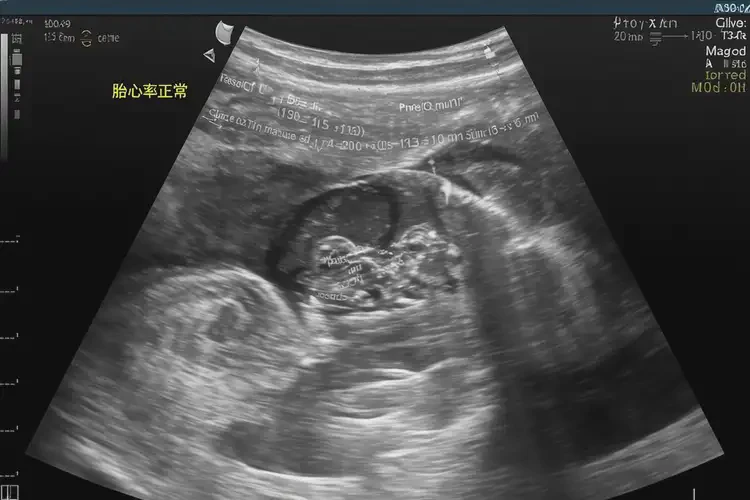

懷孕30多天胎心75有危險(xiǎn)嗎(圖1)